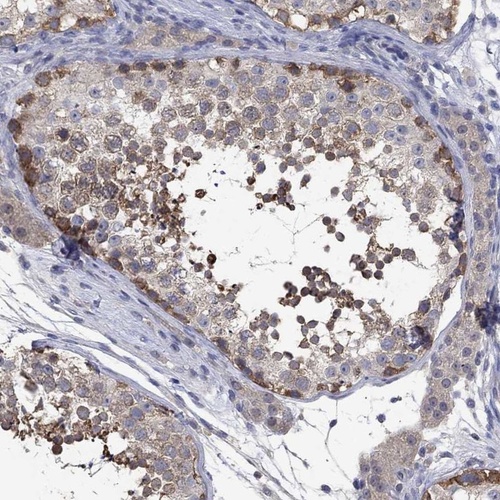

Immunohistochemistry analysis in human testis and placenta tissues using Anti-PTPN20 antibody. Corresponding PTPN20 RNA-seq data are presented for the same tissues.